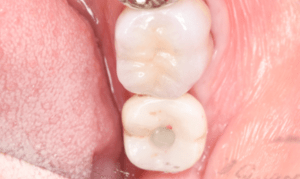

症例写真-2

- Befor

- 途中経過

- After

| 年齢 | 50代・男性 |

|---|---|

| 主訴 | 右下歯が疼く |

| 治療内容 | ・右下6番インプラント ※1:FGG(遊離歯肉移植術)とは、足りない歯ぐきを上顎から上皮を切り取り移植する外科手術 |

| 治療費 | 合計:902,000円(税込) ■内訳 |

| 治療期間 | 9ヵ月 |

| 治療方針 | 右下の当該歯は歯根破折により保存不可能と診断しました。歯周疾患も伴っていたため抜歯後に骨吸収※1が大きく起こることが予測できました。チタンメッシュ併用骨再生誘導法(GBR※2)を選択しインプラント埋入と同時に行い自然な歯槽骨のラインを再現しました。またGBRを行う際にインプラント辺縁の付着歯肉の減少が起こる為、遊離歯肉移植術(FGG※3)を行い清掃性を考慮した形態に仕上げました。 ■治療方針の解説 治療した右下の歯をレントゲンで撮影したところ根本の部分に黒く写る箇所があり「根尖性慢性周囲炎※1」と診断。また歯周病も進行していました。 ※1 骨吸収・・・歯槽骨という歯を支える骨がなくなっていくこと |

| 担当者所見 | 主訴の右下だけでなく歯茎の腫れ、発赤があり不良補綴や不良充填など他にも治療箇所が多数ありました。プラークコントロールが不良であった為まずはブラッシング指導を行いセルフケアの重要性を理解していただくところからスタートしました。 右下6番の歯はインプラント治療を行なった結果審美的にも機能的にも患者様の満足を得ることができました。骨造成と歯肉移植も行なった為インプラントを支える十分な歯周組織の獲得ができたと思っております。 |